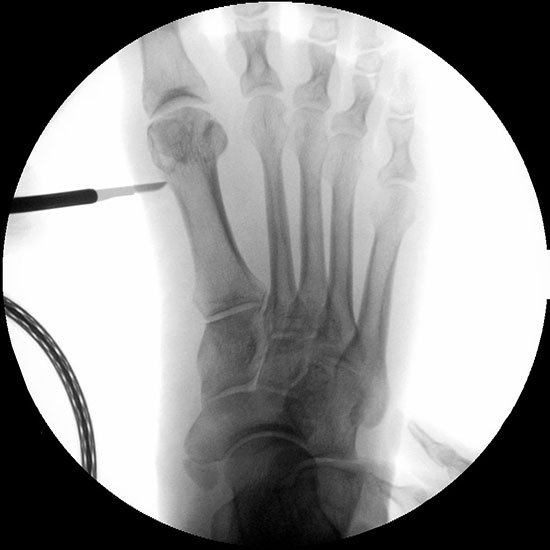

Präoperatives Röntgenbild Fuß d.p. mit eingezeichneten Winkeln. A) Intermetatarsalwinkel, B) Hallux valgus Winkel, C) Interphalangeal-Winkel.

Abbildung 2

• Operationsplanung anhand der Röntgenaufnahmen unter Beachtung wichtiger radiologischer Landmarks wie Intermetatarsalwinkel, Hallux valgus – Winkel, distaler Gelenkflächenwinkel (Distal Metatarsal Articular Angulation - DMAA), Metatarsaleindex und Sesambeinposition (Abb. 2).